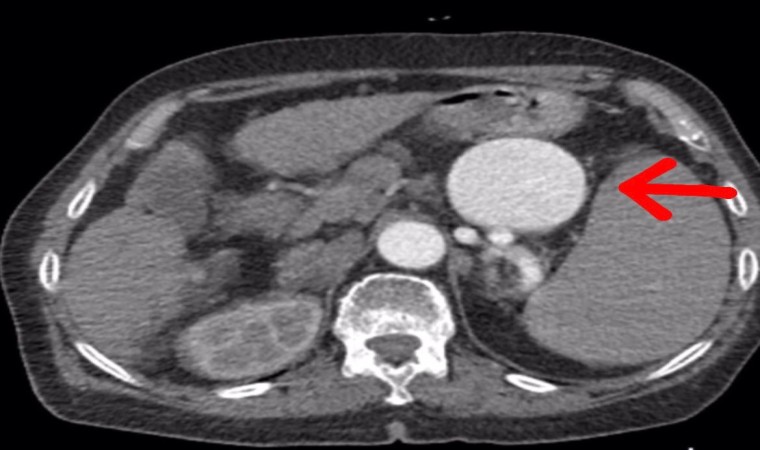

Yapılan ameliyat ile ilgili gazetecilere açıklamalarda bulunan Op. Dr. Volkan Burak Taban, hastanın gastroenteroloji kliniğinden kendilerine geldiğini, dalak arterinde ciddi bir anerizma şüphesinden bahsedildiğini söyledi. Değerlendirmeler sonrası ilaç tetkikleri istediklerini belirten Dr. Taban, "Yapılan tomografide teyzemizde dalak arterinde oldukça geniş dev diyebileceğimiz anerizmanın yani baloncuklaşmanın olduğunu gördük. Normalde dalak anerizması diyebilmemiz için baloncuklaşma diyebilmemiz için 20 milim yani 2 santimin üstüne çıkması lazım. Ama gördüğümüzde bizde şaşırdık. Çünkü yaklaşık 7 santimi geçen bir dalak anerizması vardı. Hastanın bu anerizmanın içerisinde tamamen kan dolduğu için her an patlama riski vardı. Allah korusun hastanın hayatını kaybetme riski ile de karşı karşıyaydık. Hasta ile ilgili hemen multidisipliner olarak bir değerlendirme yaptık. Hem gastroenteroloji, hem genel cerrahiden Serhat hocamız, hem radyoloji kliniğimiz ile beraber değerlendirme yaptık. Hastamızın 15 yıldır mücadele verdiği bir karaciğer sirozu da bizim kararlarımızda etkili oldu” dedi.